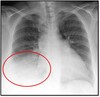

What pathology is shown here?

Bronchopneumonia ## Footnote -Is more bilateral unlike the alveolarpneumonia

What pathology is seen here?

Alveolar Pneumonia